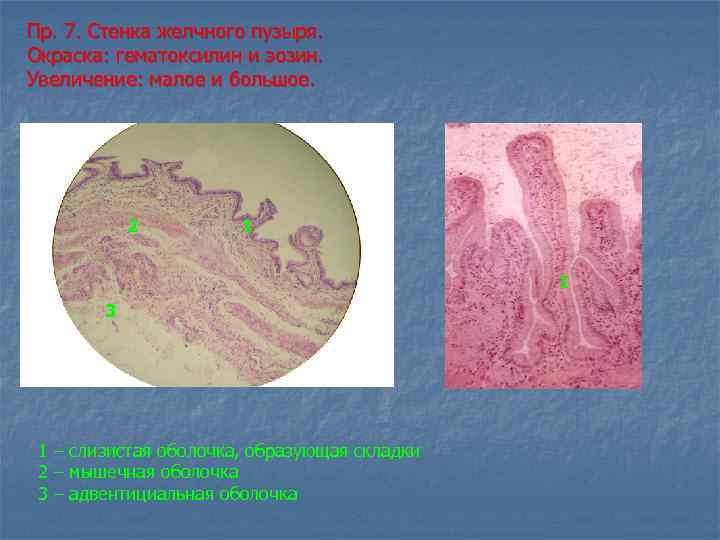

Пр. 7. Стенка желчного пузыря. Окраска: гематоксилин и эозин. Увеличение: малое и большое. 2 1 1 3 1 – слизистая оболочка, образующая складки 2 – мышечная оболочка 3 – адвентициальная оболочка